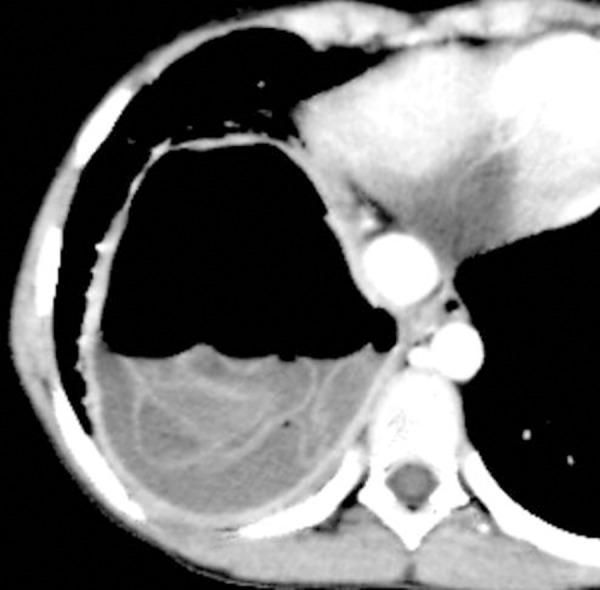

BACKGROUND The lungs are the most common site of hydatid cysts in children. Rupture is the main complication of cysts causing morbidity and mortality. In this study we aimed to comprehensively describe the CT signs for cysts and analyze the relationship of cyst ruptures to the diameter and location of cyst. MATERIAL AND METHODS A total of 145 cysts from 102 patients, aged 17 years or younger, who underwent a multi-detector computed tomography (MDCT) evaluation and had surgically proven pulmonary hydatid disease were included retrospectively. The CT images were analyzed for radiologic findings and signs of cyst rupture. RESULTS The cysts had a mean diameter of 5.45±3.03 cm. Most of the patients had a solitary cyst (70.6%). The most common lobes involved were the lower lobes (58.6%). Peripherally located cysts were more common than central cysts. The overall number of ruptured cysts was 69 (47.5%). The most common sign was the waterlily sign with a prevalence of 24.6%. After exclusion of cysts of 1 cm, the mean cyst diameter was 6.23±2.83 cm in the unruptured group and 5.02±2.80 cm in the complete ruptured group (p=0.020). The mean cyst diameter was 6.38±3.11 cm for centrally located cysts, and 4.31±2.37 cm for peripherally located cysts (p<0.0001). CONCLUSIONS Pulmonary hydatid cysts commonly presents as solitary cysts with a predilection for lower lobes and the peripheral regions of the lung. Peripherally located cysts are more common but smaller than centrally located cysts. Radiologists should also be aware of atypical imaging findings of cyst rupture, and radiologic signs should be explored during radiologic evaluation.

摘要

背景

肺部是儿童包虫囊肿最常见的部位。破裂是囊肿的主要并发症,可导致发病率和死亡率。在本研究中,我们旨在全面描述囊肿的 CT 征象,并分析囊肿破裂与囊肿直径和位置的关系。

材料和方法

回顾性分析了 102 例年龄在 17 岁以下的经多排 CT(MDCT)检查并经手术证实为肺包虫病的患者的 145 个囊肿。对 CT 图像进行了影像学表现和囊肿破裂的影像学征象分析。

结果

囊肿的平均直径为 5.45±3.03cm。大多数患者为单发囊肿(70.6%)。最常见的受累肺叶是下叶(58.6%)。周围部位的囊肿比中央部位的囊肿更常见。破裂的囊肿总数为 69 个(47.5%)。最常见的征象是睡莲征,发生率为 24.6%。排除直径为 1cm 的囊肿后,未破裂组的平均囊肿直径为 6.23±2.83cm,完全破裂组为 5.02±2.80cm(p=0.020)。中央部位囊肿的平均直径为 6.38±3.11cm,周围部位囊肿的平均直径为 4.31±2.37cm(p<0.0001)。

结论

肺包虫囊肿常表现为单发囊肿,以下叶和肺外周区域为好发部位。周围部位的囊肿比中央部位的囊肿更常见,但体积更小。放射科医生也应该注意到囊肿破裂的不典型影像学表现,在影像学评估中应该探索影像学征象。